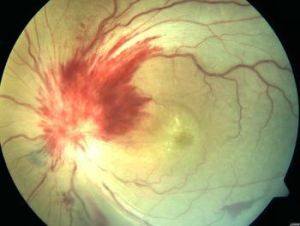

患者性別無差異。大多為單側性,病眼視力自幼高度不良,中心視力在眼前指數至0.02之間。常因此而發生先天性斜視。往往伴有高度近視、眼球類震顫等。在檢驗鏡下,視乳頭面積明顯擴大,一般達4~5PD。呈粉紅色,中央有漏斗狀凹陷,凹陷底部被棉花絨樣物質充填。有十餘支或二十餘支粗細不等的血管自充填物邊緣穿出,徑直走向周邊部,動靜脈難以分清。視乳頭周圍有一寬闊的黃白色或灰黑色環狀隆起。其中有色素斑塊。外周更有與之呈同心圓的脈絡膜視網膜萎縮區。黃斑被累及。FFA見不到凹陷中央被棉花絨樣填充物所遮蔽的血管,但在填充物較為稀薄者,可隱約透見視網膜大血管分支。因此,Krause(1972年)認為此等異常血管來自視網膜中央血管,而不是睫狀血管。

眼底表現酷似一朵盛開的牽牛花,視盤比正常的擴大3-5倍,呈漏斗狀,周邊粉紅色,底部白色絨樣組織填充。血管呈放射狀,動靜脈分不清。視盤周圍有色及萎縮區。可伴有其他眼部先天性異常。